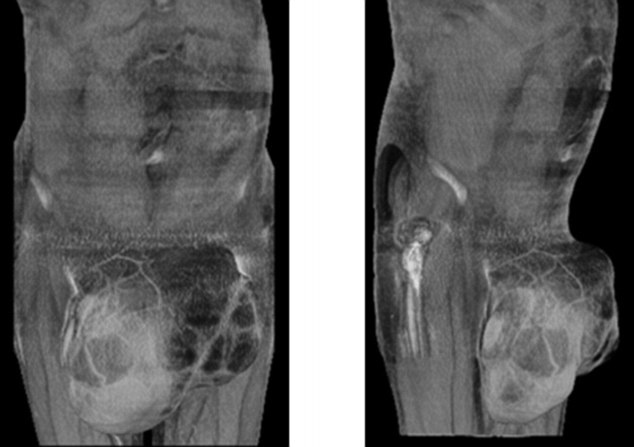

Bob đã gặp một bác sĩ tiết niệu tại bệnh viện Liverpool Broadgreen vào cuối tháng 12. Bác sĩ chuẩn đoán ông mắc bệnh sarcoma, một loại ung thư hiếm gặp của các mô, cơ và xương. Sau khi kiểm tra vài lần, bác sĩ chỉ định ông phẫu thuật vào tháng 2. Tuy nhiên, hôm 25/6, các bác sĩ phẫu thuật tại Bệnh viện Hoàng gia Liverpool mới cắt khối u 4 kg tại bìu của ông.

| Bác sĩ chuẩn đoán ông mắc bệnh sarcoma, một loại ung thư hiếm gặp của các mô, cơ và xương. Ảnh: Dailymail. |